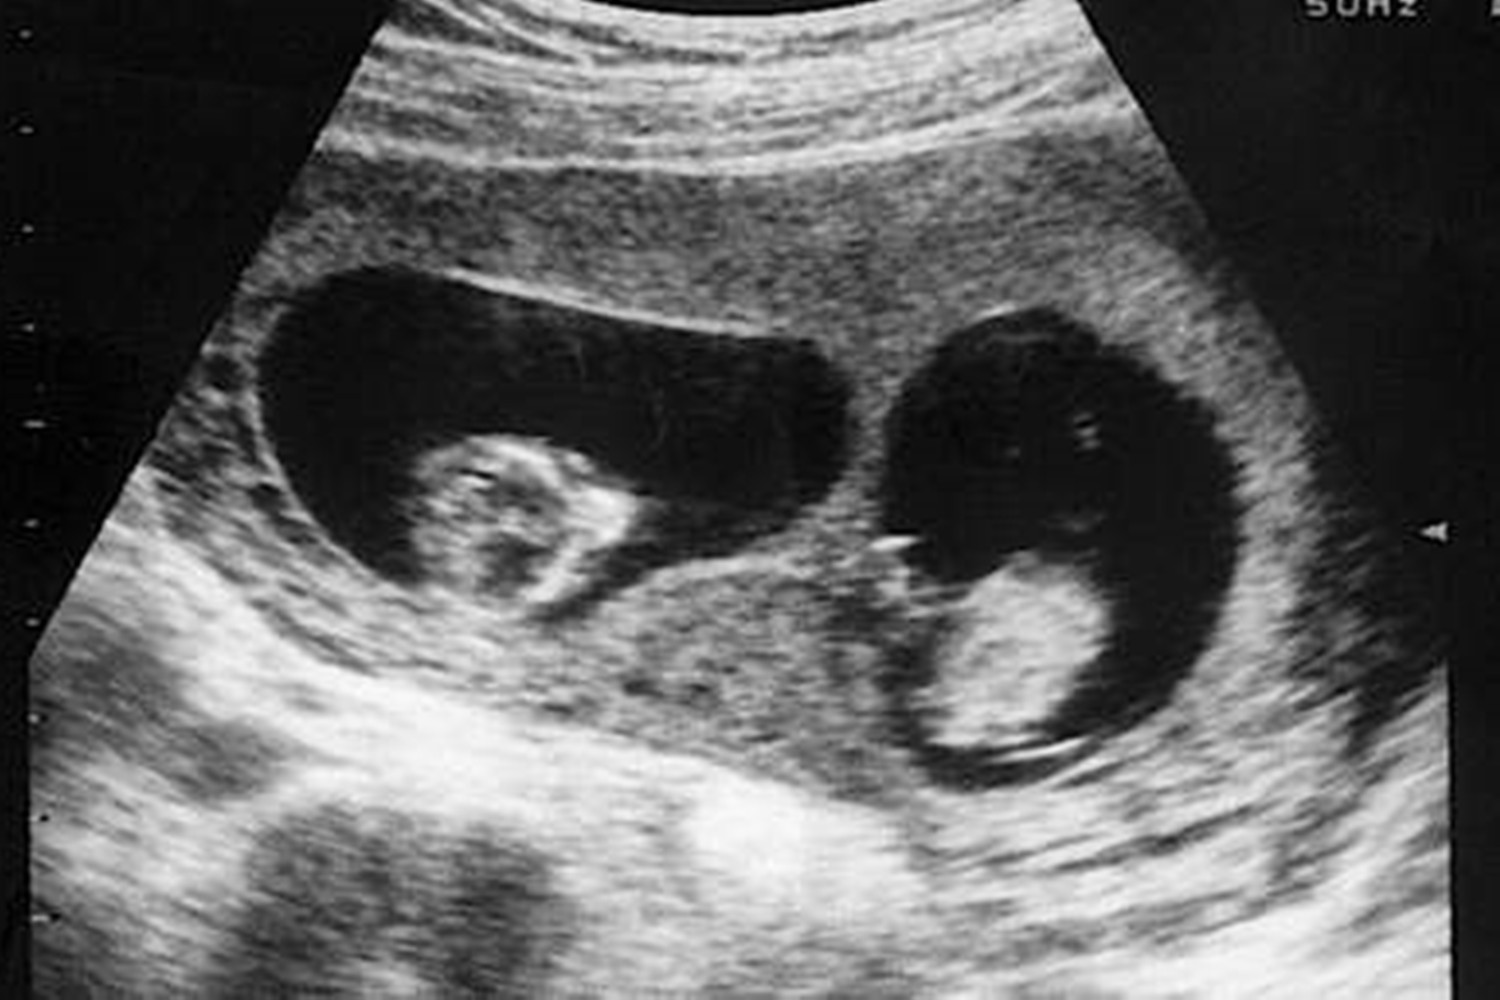

检查时医生称肚中有两个胚胎,得知此消息孕妈及家属的心情都十分美好。

但事情没过多久就迎来了转折,之后做产检时,吉文斯查看B超影像发现两个胎儿的发育相差很大,姐姐弱弟弟强。

医生面带遗憾地跟她说:目前我们只能听到一个胎心音了。无法接受这一结果的吉文斯,又去其他医院反复检查过好几次,但结论仍然一样。

到了怀孕第13周,检查后医生称,超声影像显示腹中只存在一个胎儿了,另一个已死去并被吸收。

上文的例子属于第三种,医学上称为“双胎消失综合征”,指的是双胞胎中的一个发生流产,且组织被母体或另一个胎儿吸收的现象。多发于年龄在30岁左右且生育过多个孩子的产妇身上,概率为20%~30%。